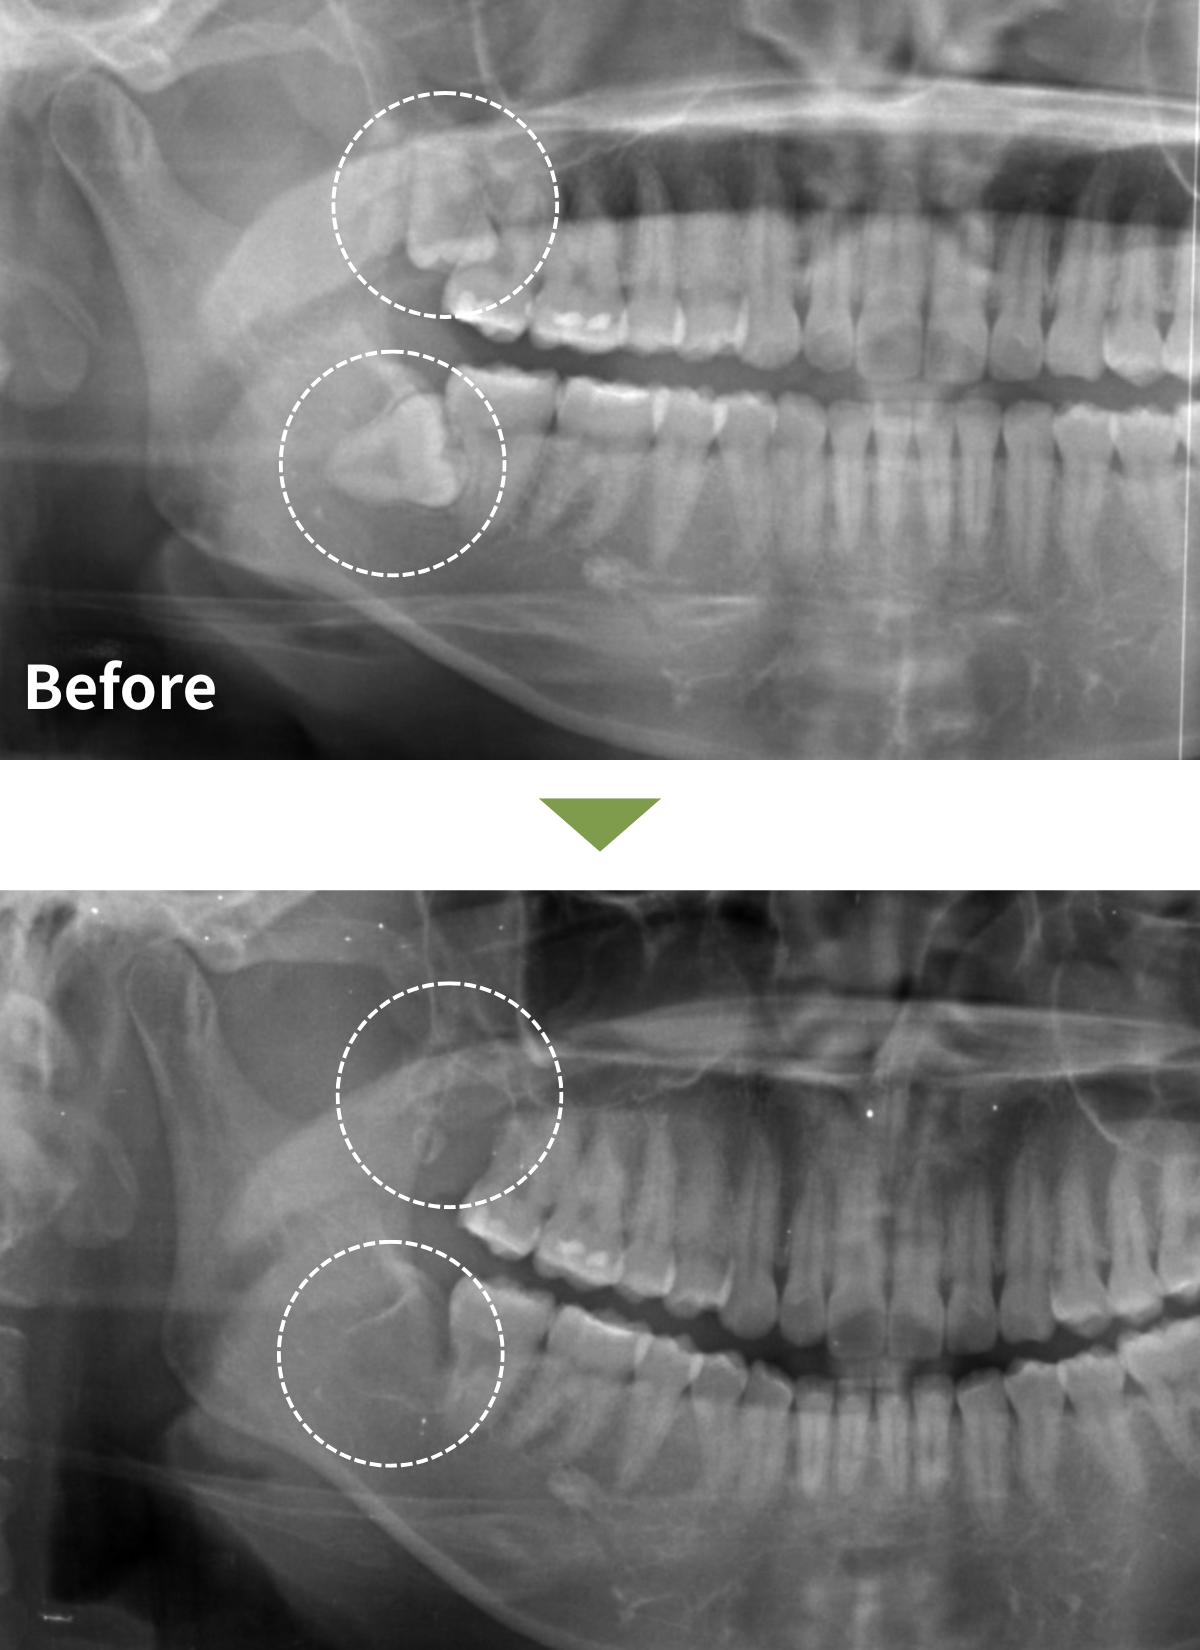

| 治療名 | 上顎・下顎右側の親知らず(完全埋伏智歯)抜歯術 |

|---|---|

| 患者様情報 | 20代女性 |

| 執刀医 | Dr. 井出 |

| 治療内容 |

当院矯正治療中で、矯正のため親知らず抜歯が必要となり当院で抜歯を行うことになった。 口腔内所見は上下ともに完全埋伏していた。 CT検査の結果8┘根尖部が上顎洞底と接していた。また8┐は下歯槽神経と交差しており、深く埋伏していた。 |

| 症例写真 |

|

| 治療期間 | 30分 |

| 治療経過 | 抜歯後1週間で抜糸を行いました。 経過は良好で、痛みや腫れも落ち着いています。 抜歯部は下歯槽神経や上顎洞に近い位置でしたが、神経麻痺や上顎洞への影響などの症状はみられませんでした。 |

| リスク | 腫れ、痛み、出血、感染、下唇やあごのしびれなどの神経麻痺が生じる場合があります。 |